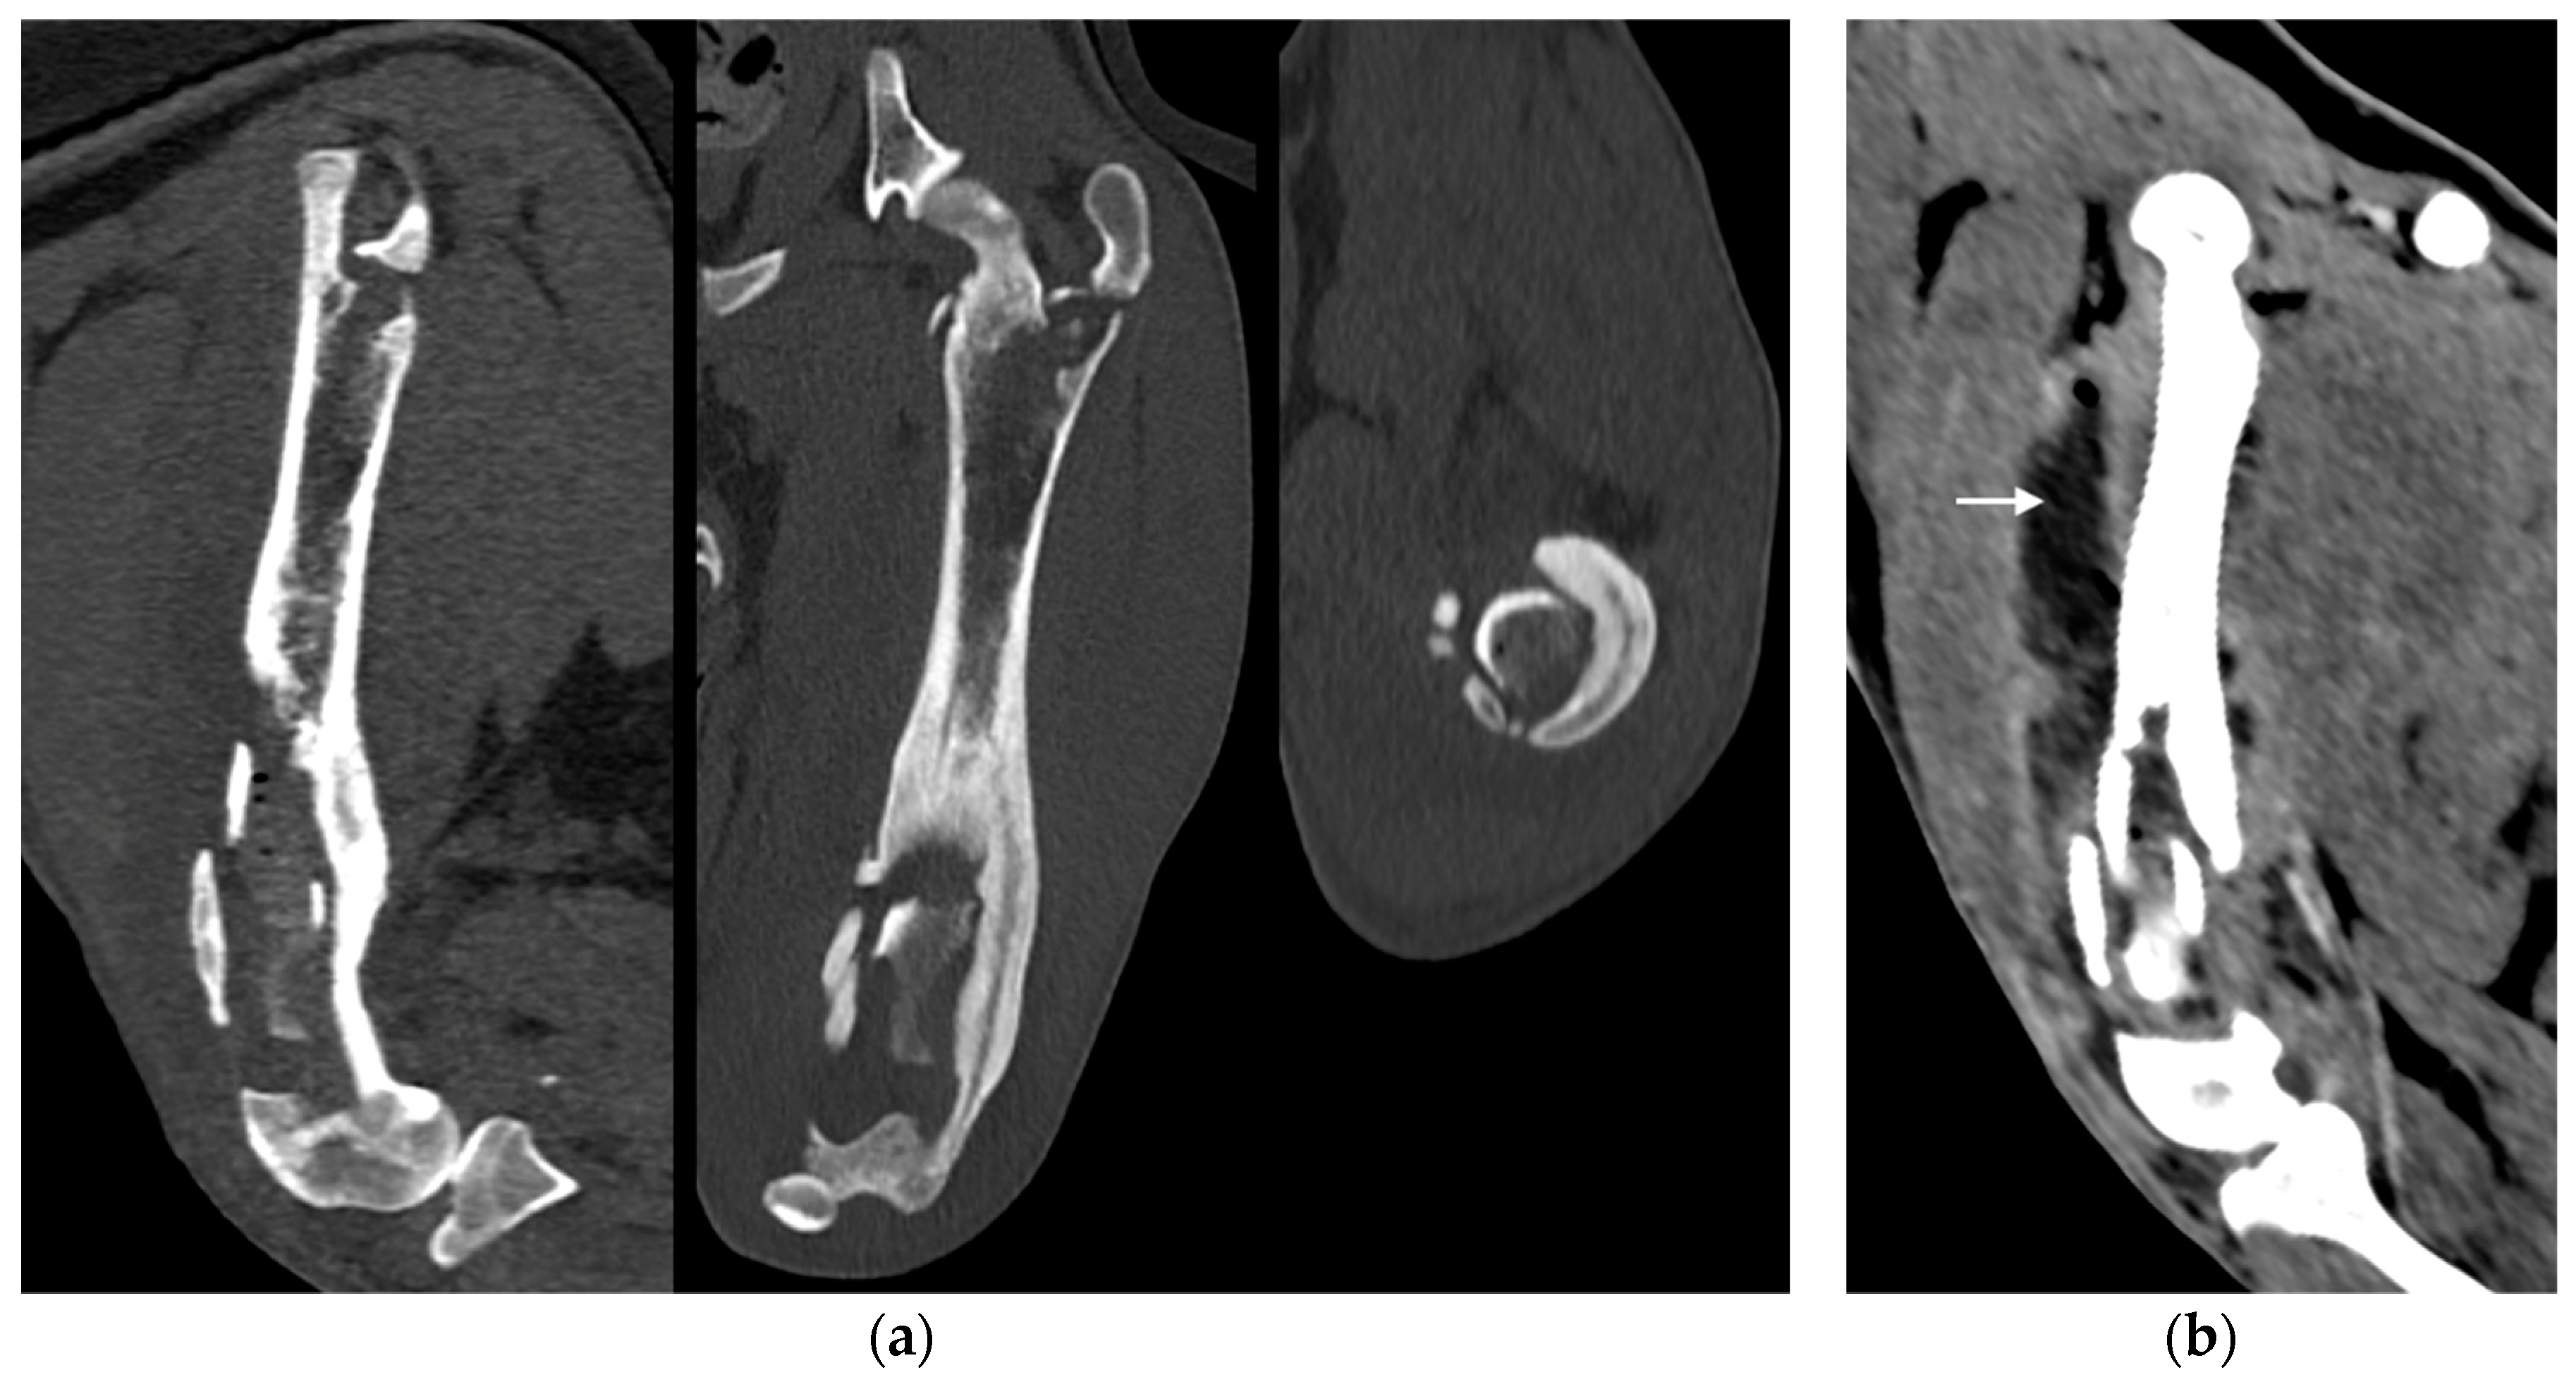

Under anesthesia, a computed tomography study (CT; Somatom Emotion 16, Siemens, Germany) of the hind limbs was performed. The tomographic images revealed medullary osteolysis of the metaphysis and the distal-middle third of the femoral diaphysis. In the metaphysis and the distal third of the femoral diaphysis a bone sequestrum was found: a wide interruption of the cranio-medial cortical profile, with involvement of the femoral trochlea, was observed with corticomedullar fragment of 4 x 1.4 cm (length x width) medially dislocated at the level of the medullary cavity; the fragment was surrounded by a large hypodense halo. Secondary MPL and widespread subcutaneous and perifascial abscess lesion were also reported (Figure 3).

Figure 3. (a) Sagittal, frontal and transverse tomographic images of the metaphysis and the distal-middle third of the femoral diaphysis revealed medullary osteolysis, a wide interruption of the cranio-medial cortical profile with corticomedullar fragment of 4 x 1.4 cm (length x width) medially dislocated at the level of the medullary cavity (bone sequestrum), and an extensive periosteal reaction of caudo-lateral cortex of the femoral distal diaphysis. (b) A widespread subcutaneous and perifascial abscess lesion were also reported (white arrow).